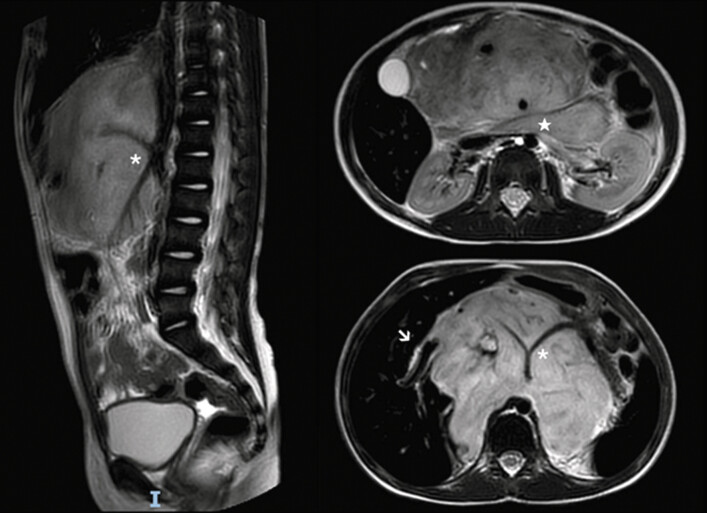

我们报告了一名6岁儿童在腹部神经母细胞瘤(NB)切除术中因术中损伤而继发的胆总管(CBD)造口后狭窄的应用内镜胆囊十二指肠吻合术。患者被诊断为M期NB,特点是骨髓和椎骨播散,MYCN扩增。经过多个周期的化疗和随后的造血干细胞移植,患者计划手术切除。术前影像学检查确定了几个影像学确定的危险因素,包括肝门浸润和十二指肠胰复合体浸润。在切除肿瘤过程中,发生了CBD的意外损伤,随后通过端到端吻合修复。术后7个月,患者因吻合口狭窄而出现梗阻性黄疸,通过在扩张的胆囊和十二指肠之间放置超声内镜引导的腔内金属支架(LAMS)成功控制。根据我们的经验,内镜胆囊十二指肠吻合术是解决小儿术后医源性CBD狭窄的一种新方法。有必要进一步研究以阐明其益处和风险,并评估其长期疗效和更广泛应用的潜力。

We report the use of endoscopic cholecystoduodenostomy in a 6-year-old child to manage postanastomotic stricture of the common bile duct (CBD) secondary to an intraoperative injury sustained during the resection of an abdominal neuroblastoma (NB). The patient was diagnosed with stage M NB, characterized by dissemination to the bone marrow and vertebrae, and MYCN amplification. Following multiple cycles of chemotherapy and subsequent hematopoietic stem cell transplantation, the patient was scheduled for surgical resection. Preoperative imaging identified several image-defined risk factors, including infiltration of the porta hepatis and of the duodenopancreatic complex. During the dissection of the tumor, an incidental injury to the CBD occurred, which was subsequently repaired via end-to-end anastomosis. Seven months postoperatively, the patient presented with obstructive jaundice due to an anastomotic stricture, which was successfully managed through the placement of an endoscopic ultrasound-guided lumen-apposing metal stent (LAMS) between the dilated gallbladder and the duodenum. In our experience, endoscopic cholecystoduodenostomy constitutes a novel approach for addressing postoperative iatrogenic CBD strictures in pediatric patients. Further research is warranted to elucidate its benefits and risks as well as to evaluate its long-term efficacy and potential for broader application.